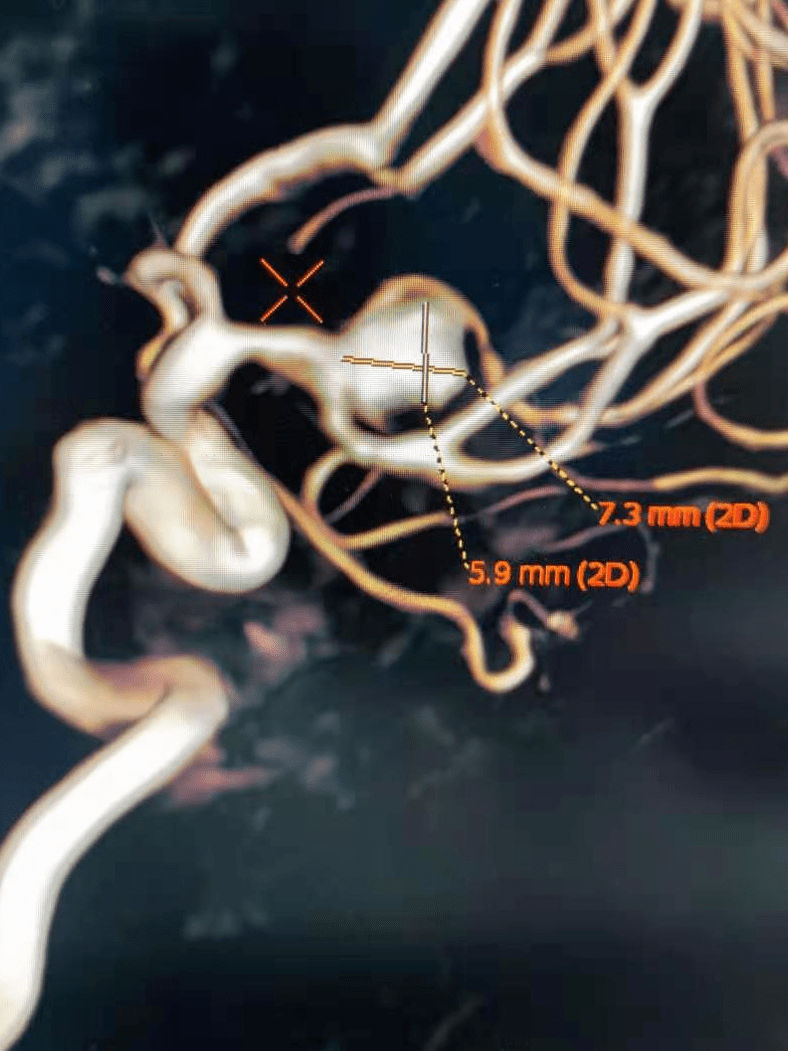

atlas病例集孙勇小径输送更远更细右侧胼周动脉分叉部微小动脉瘤支架

atlas病例集丨徐翔曲径通幽小身材大担当atlas支架在小直径血管内的